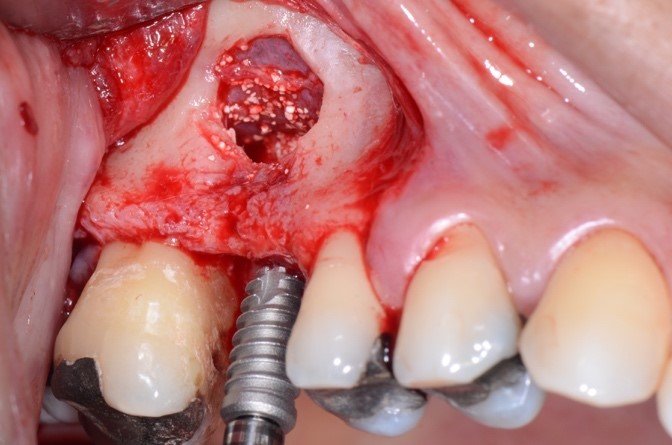

A irrigação da maxila é realizada por ramos de 2 principais vasos, a artéria alveolar superior posterior (AAPS) e a artéria infra-orbital (AIO), ramos da artéria maxilar 3,4. No estudo com tomografias de Khojastehpour et al 5 em 2016, eles encontraram anastomose na membrana entre as artérias AAPS e a AIO em 49.8% dos indivíduos, e do ponto de vista técnico nesssa condição, somente em casos de acidentes com rompimento da membrana sinusal poderia ocorrer hemorragias relevantes. Por outro lado, outros autores têm encontrado maior número de situações em que a AAPS se encontra intra-óssea, como nos estudos de Güncü et al 6 em 2011, e Ilgüi et al 7 em 2013, que observaram 68.2% e 71.1%, respectivamente. Quando a AAPS se encontra nessa última condição relatada, ocorre maior risco de dano vascular com hemorragia, especialmente se o canal vascular intra-ósseo for maior que 1 mm de espessura. Em média, alguns estudos têm demonstrado que a distância vertical do canal vascular da AAPS se apresenta próximo de 16 mm 5,7. Porém em casos de reabsorção do rebordo alveolar essa altura pode ser encontrada próximo de 11mm, segundo Rosano et al 4. A recomendação da tomografia como imagem de diagnóstico para identificação e mensuração da AAPS, pode estabelecer modificações estratégicas tanto na osteotomia, em relação ao desenho vertical e comprimento do implante, quanto na metodologia de instrumentação óssea. Podem ser usadas, por exemplo, ponteiras piezoelétricas sob irrigação para melhorar a visualização operatória e diminuir o risco de laceração vascular. As figuras de 1 a 12, demonstram caso clínico de técnica cirúrgica com osteotomia modificada, usando unidade piezo Mectron para remoção da parede lateral e preservar a AAPS, que foi diagnosticada em exame tomográfico durante a fase pré-operatória.

As figuras 16 e 17 mostram o transoperatório de um caso de hemorragia após dano a AAPS durante procedimento de osteotomia para rotação superior da janela óssea. A hemorragia durante a cirurgia trouxe dificuldades na visualização da membrana e a mobilização da janela para o interior da cavidade para formar o teto sobre a membrana sinusal. Somente após o preenchimento total com enxerto ósseo bovino particulado e cobertura com membrana hemostática de colágeno, houve diminuição do fluxo sanguíneo local. Mesmo com a manobra transoperatória, ocorreu a formação de extenso blefarohematoma periorbital e hematoma cérvico-facial. Segundo relato da paciente, o edema palpebral e na região parotídeo-masseterina provocaram dificuldade na abertura palpebral e bucal. As figuras 18 e 19 demonstram os hematomas já em regressão no 110 dia de pós-operatório (PO), já em uso de compressas mornas desde o 70 dia de PO, associado a moderada massagem local para drenagem hemo-linfática nos tecidos com pomada fibrinolítica.